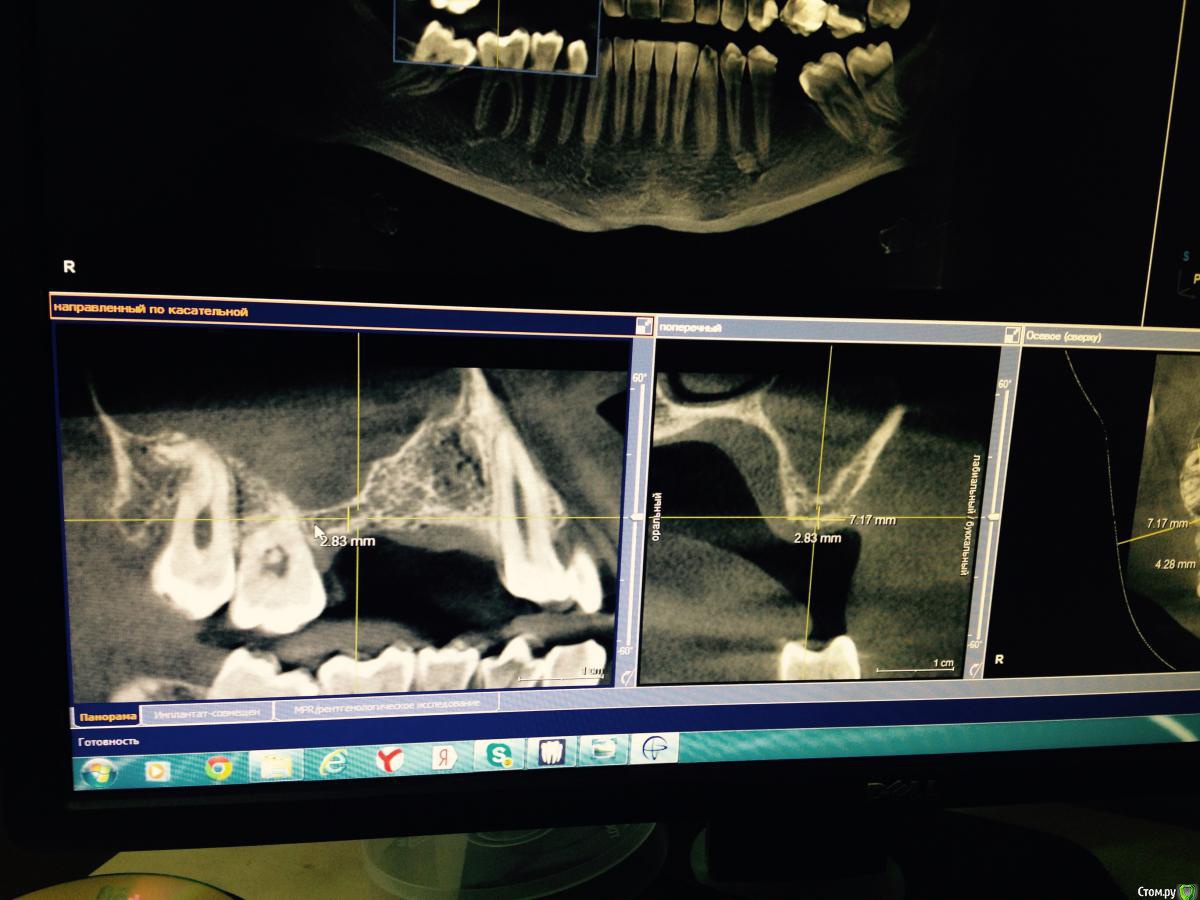

Robinbobin Опубликовано 25 марта, 2015 Автор Поделиться Опубликовано 25 марта, 2015 я бы обошелся без вертикального разреза, и делал бы разрез по гребню. Почему делали открытый синус? Я делал разрез по гребню но из-за маленького опыта порвал((((Делал открытый потому что объем кости был 2-2.5 мм а боком поставить побоялся) Ссылка на комментарий

red_butler Опубликовано 25 марта, 2015 Поделиться Опубликовано 25 марта, 2015 Делал открытый потому что объем кости был 2-2.5 мм а боком поставить побоялся) все, увидел, конечно открытый Ссылка на комментарий

Robinbobin Опубликовано 25 марта, 2015 Автор Поделиться Опубликовано 25 марта, 2015 (изменено) Да все отлично только овертритмент ИМХОhttp://s018.radikal.ru/i510/1503/69/a152c76082f0.png то же самое только без синусаОчень сложно так поставить в такой ситуации по крайней мере для меня Изменено 25 марта, 2015 пользователем Robinbobin Ссылка на комментарий